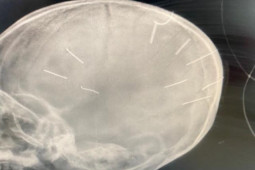

Ngày 20/1, Phòng Cảnh sát hình sự, Công an TP Hà Nội cho biết đã tiếp nhận hồ sơ từ Cơ quan CSĐT Công an huyện Thạch Thất về vụ bé gái 3 tuổi ở xã Canh Nậu, huyện Thạch Thất bị phát hiện trong sọ não có nhiều vật thể lạ nghi là đinh.

Trước đó, ngày 18/1, Công an huyện Thạch Thất, Hà Nội tiếp nhận thông tin phản ánh từ Bệnh viện đa khoa huyện Thạch Thất về việc có 1 bé gái 3 tuổi nhập viện trong tình trạng sức khỏe xấu. Qua hình ảnh chụp chiếu, Bệnh viện xác định trong sọ bé gái có nhiều vật thể lạ trông giống đinh. Công an huyện Thạch Thất đã triệu tập mẹ cháu và bạn trai là Nguyễn Trung H cùng một số cá nhân được cho liên quan đến sự việc và khẩn trương phối hợp cùng các cơ quan chức năng tiến hành điều tra.

Theo thông tin ban đầu, khoảng 17h23 ngày 17/1, khoa Cấp cứu Bệnh viện đa khoa Thạch Thất tiếp nhận bé gái Đ.N.A, 3 tuổi, trú ở xã Canh Nậu, huyện Thạch Thất được mẹ đưa đến trong tình trạng hôn mê, co giật.Theo trình bày của người mẹ, từ chiều cùng ngày đã thấy bé A. có biểu hiện bất thường, gọi liên tục nhưng bé không tỉnh. Bệnh viện Đa khoa huyện Thạch Thất tiến hành chiếu chụp, chẩn đoán trên phim có hình ảnh cản quang trên hộp sọ bệnh nhi.

Rạng sáng 18/1, bé A. đã được chuyển đến Bệnh viện đa khoa Xanh Pôn. Một nguồn tin cho biết, Bệnh viện đã tiến hành chụp cắt lớp, nhận thấy có những hình ảnh như những chiếc đinh, và tiên lượng sức khỏe của bé A. không tốt.